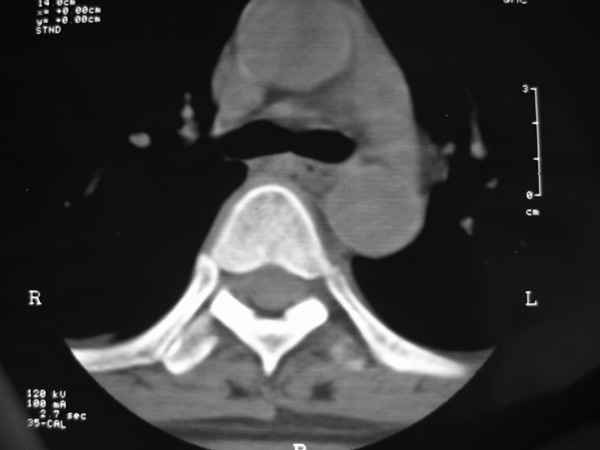

女,45岁,胸背部疼痛2个月。t6、7胸椎病变。

椎旁肿胀的软组织内可见气泡影,对脊柱的化脓性和结核性的鉴别有帮助吗?

胸椎结核与脊柱椎体化脓性脊柱炎,从影像特点很难鉴别,本例具有二者的共性特点,建议结合临床鉴别以下,我考虑:1 化脓性脊柱炎.2 胸椎结核.原因:1 椎旁脓肿内含气泡.2 椎体溶骨性破坏,但未见死骨.

胸椎体骨质破坏伴死骨形成,椎周环状软组织肿胀,范围较长,考虑胸椎结核伴冷脓肿形成。鉴别;1转移性肿瘤;椎弓根骨质破坏多见,软组织肿块局限。椎间隙尚存。有原发肿瘤病史。2,淋巴瘤;骨质破坏 然骨皮质轮廓线尚存,当椎管骨示环状软组织影时有一定特异性。病变较局限。建议mri增强,观察冷脓肿与软组织肿块很有帮助。

胸椎结核伴冷脓肿形成且侵入椎管。